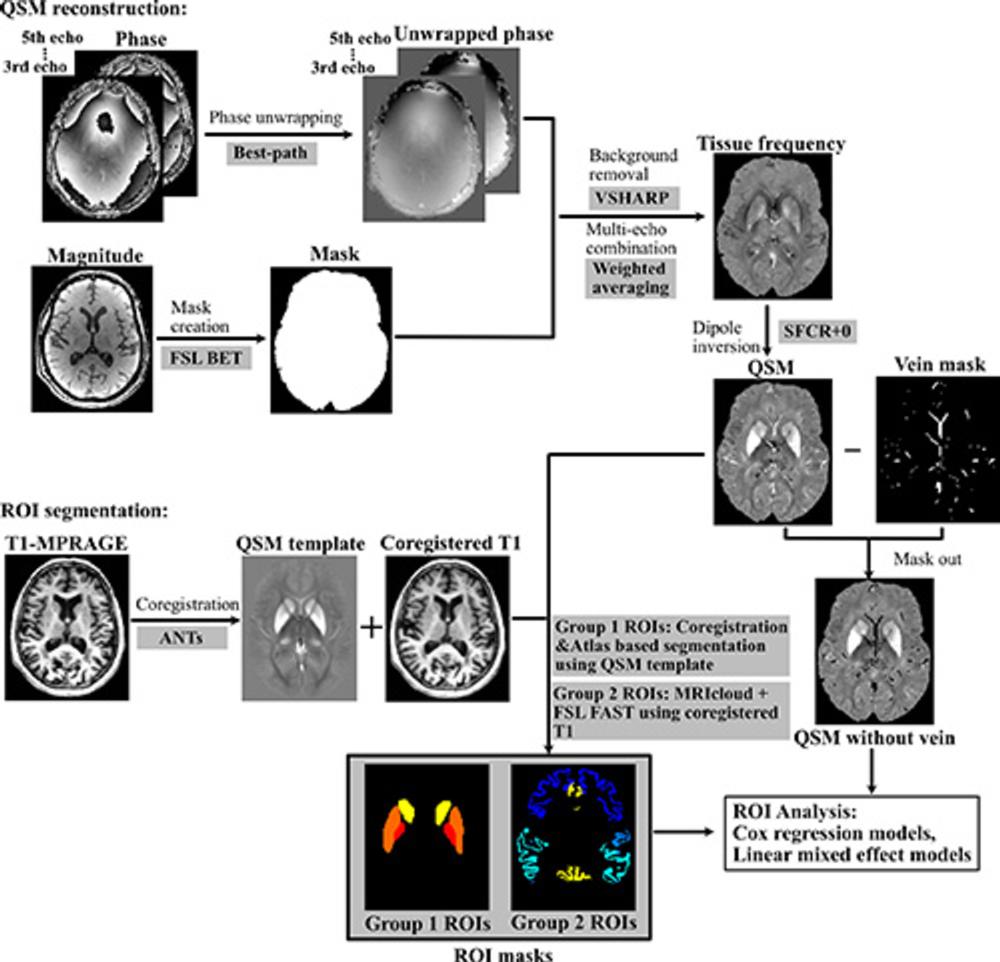

Figure 2. Processing pipeline for quantitative susceptibility mapping (QSM) reconstruction and region-of-interest (ROI) segmentation MRICloud is cloud-based medical image processing software (mricloud.org). ANT = advanced normalization tool, BET = brain extraction tool, FAST = functional MRI of the brain automated segmentation tool, FSL = functional MRI of the brain software library, MPRAGE = magnetization-prepared rapid gradient-echo, SFCR+0 = structural feature–based collaborative reconstruction with auto referencing to central cerebrospinal fluid, VSHARP = variable radius sophisticated harmonic artifact reduction for phase data.